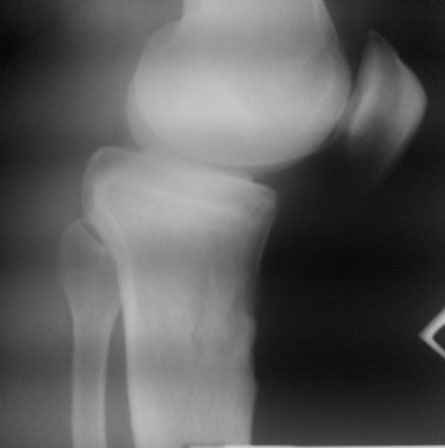

Доктора, предлагаю обсудить клинический случай. Мужчина 1960 гр в возрасте 10-12 лет получает травму, которую сейчас описать точно не может, не помнит.

В настоящий момент единственная, как ни странно, жалоба – появление кисты Бейкера. А еще больше косметический дефект. Собственно, с идеей коррекции косметического дефекта пациент к нам и обратился.

По видимому, тогда было повреждение задней крестообразной связки, рекурвация голени стала устойчивой, плато имеет неправильный угол наклона, а в верхней трети большеберцовой кости формируется маршевый перелом.

Объективно. Боли при пальпации нет, движения практически в полном объеме. Рекурвация внешне совершенно очевидная. Положение голени устойчивое.

Растущая киста Бейкера говорит о начале декомпенсации со стороны сустава, как я понимаю.

Что мы можем предложить пациенту. Ваши прогнозы по развитию маршевого перелома. Стоит ли сейчас предлагать коррекцию рекурвации. Что делать с «задним выдвижным положением», ибо это уже не «ящик». Нет даже колебания вперед-назад.

простите, мне и самому кажется, что качество снимков не лучшее.